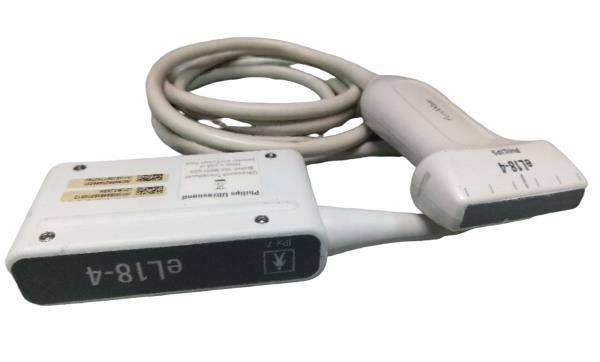

Probe frequency: 2.5~10.0 MHz

Optional: Convex probe 3.5MHz: Linear probe 7.5MHz/Transvaginal probe 6.5MHz